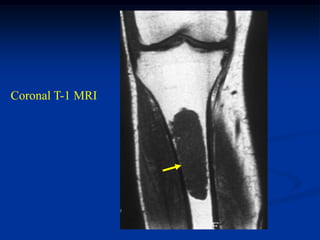

Coronal T-1 MRI

tumor

Axial T-2 MRI